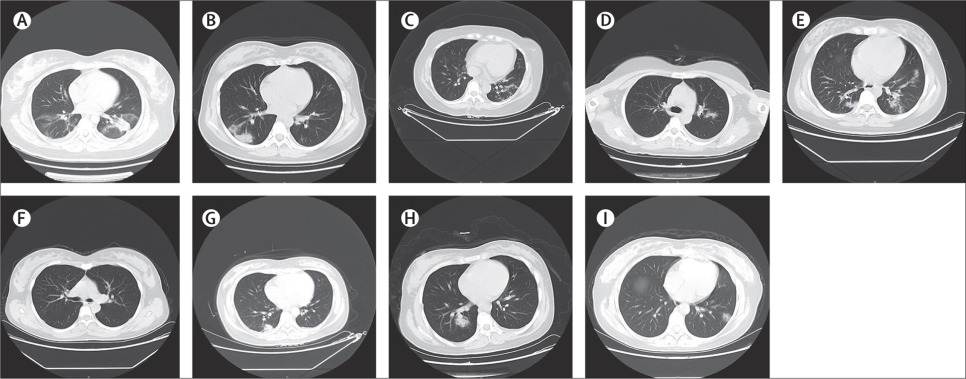

所有9例患者均进行了胸部CT扫描。 8例患者表现出胸部CT图像的典型发现-肺部有多个斑片状玻璃阴影。没有观察到胎儿死亡,新生儿死亡或新生儿窒息。 四名患者有早产,但均超过妊娠36周。所有9个活产婴儿的1分钟Apgar评分为8-9分,5分钟Apgar评分为9-10分。新生儿1出生时心肌酶(肌红蛋白170.8ng/mL,肌酸激酶心肌带8.5ng/mL)轻度升高,但无临床症状。从6名患者采集的羊水、脐血、新生儿咽拭子和母乳样本中检测SARS-CoV-2的存在。CDC推荐的试剂盒和我们的内部巢式RT-PCR检测均未在这些样本中检测到SARS-CoV-2。